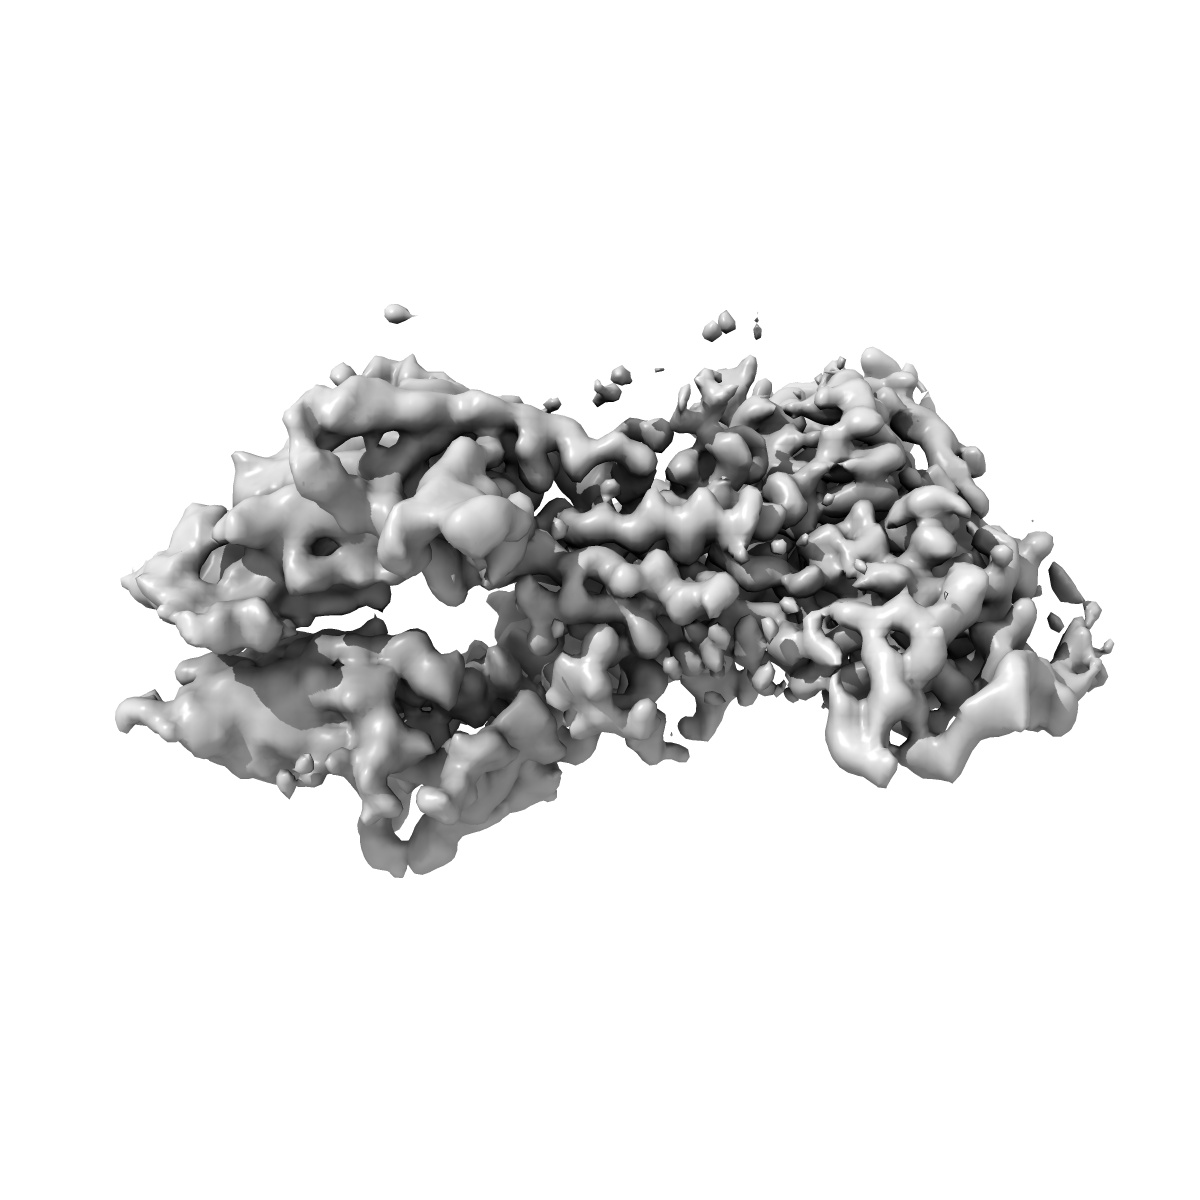

Cryo-EM structure of murine Thrombopoietin receptor ectodomain in complex with Tpo

Single-particle3.6 Å

Sample: 2:1 complex of the mouse thrombopoietin receptor ectodomain and mouse thrombopoietin

Cryo-EM structure of the extracellular domain of murine Thrombopoietin Receptor in complex with Thrombopoietin.